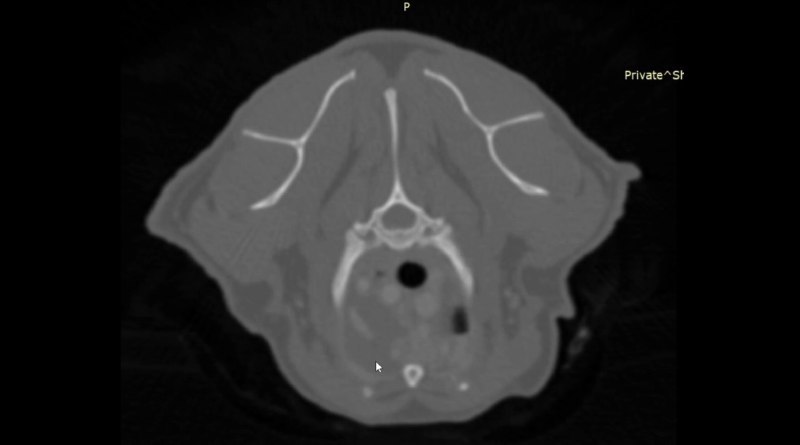

Компьютерная томография грудной клетки Описание:

• Плевральная полость: контуры париетальной плееры бугристые выражено утолщены и с гиперперфузией - паттерн «скомканного полотенца» наибольший объем которого характерно располагается вентрально каудально за сердцем (в области кардиодиафрагмального контакта); характерный паттерн пролиферации и его распределение для пиоторакса; двусторонний плевральный выпот в умеренном на момент исследования количеств.

о Полный компрессионный ателектаз КрЛеД с сохраненной перфузией и нормальными остроугольными краями

о Выраженные компрессионные уплотнения легочной паренхимы в вентральных сегментах всех прочих легочных долей ассоциированные с плевральным выпотом

о Сердце незначительно смещено дорсально за счет объема пролиферации мягкой ткани (фиброзная ткань наиболее вероятна)

о Стернальный лимфоузел: выраженное увеличение без четких контуров и область пролиферации мягкой ткани в их проекции, характерное для пиоторакса у кошек

1. KТ признаки пиоторакса в фиброзно-экссудативной стадии с выраженной фиброзной пролиферацией

2. Двусторонний плевральный выпот и компрессионные изменения легких

3. Признаков неопластического / метастатического роста не визуализируется

- Представленный паттерн пролиферации мягкой ткани париетальной плевры не является абсолютно патогномоничным, но в значительно большей степени характерен именно для фиброзной пролиферации, почти всегда формирующемся у кошек при пиотораксе. Окончательная (официальная) верификация возможна только по p-там гистологического исследования, но оно редко проводится у подобных пациентов.

- Кошкам с такими находками строго рекомендована установка двусторонних плевральных дренажей и стационарное печение